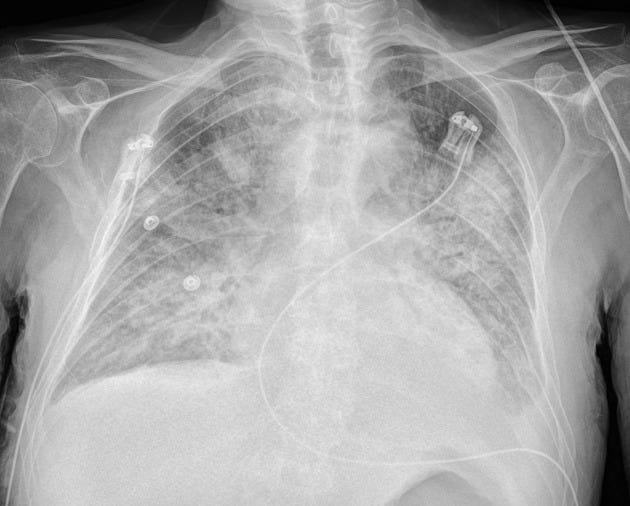

A chest radiograph is performed: